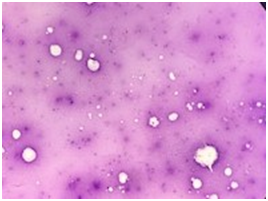

The case was referred to our laboratory for flowcytometry to rule out plasma cell dyscrasia. Examination of the bone marrow aspirate shows Pinkish Amorphous background with ghost like cells, accordingly bone marrow Necrosis was suspected Figure 2. Flowcytometry was done on the Bone Marrow sample despite the findings. It showed Majority of the population are present in the CD45 region with Absence of CD34, CD99, CD56 and plasma cell Markers Figure 3, since flowcytometry was not informative atrial of flowcytometry was done from Peripheral blood too and it was also negative for Plasma cell Markers (CD19, CD38, CD138, and CD56) & immature markers such as CD34 & CD117. It only showed slight increase in CD56 positive NK cells (27%) in the lymphocytic gate.

Figure 2 Extensive bone marrow aspirate necrosis with large areas of ghost cells in a background of amorphous eosinophilic material.